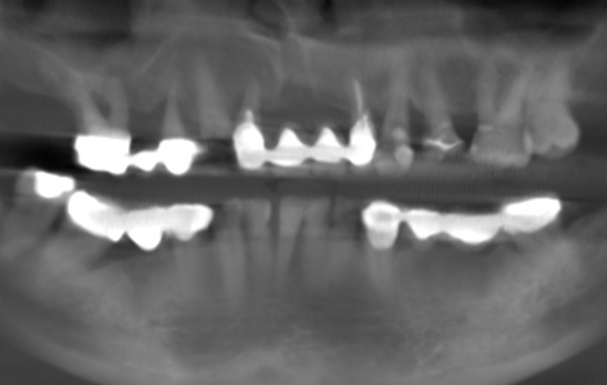

Foto 1. Perdita ossea radiografica avanzata, con difetti di tipo verticale a carico di diversi elementi, soprattutto gli elementi 16, 14 e 12 pilastri di ponte.

Foto 1. Perdita ossea radiografica avanzata, con difetti di tipo verticale a carico di diversi elementi, soprattutto gli elementi 16, 14 e 12 pilastri di ponte.